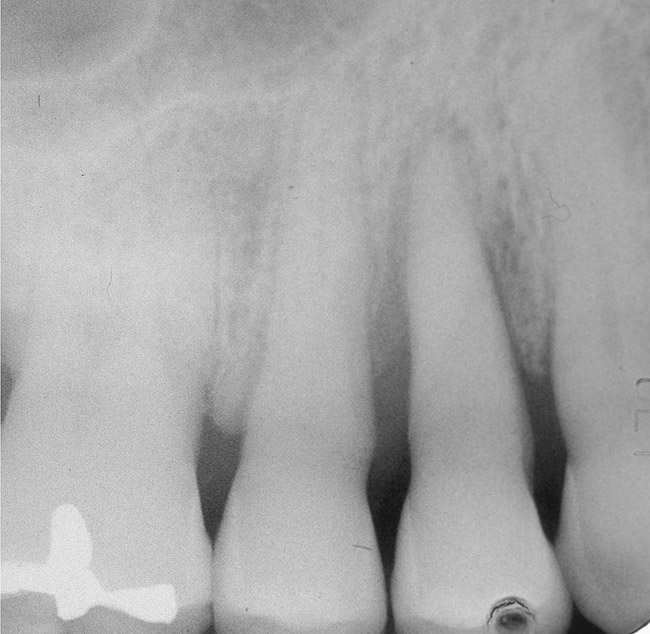

Figure 1  Tooth No. 5 showing advanced periodontal bone loss and a widened periodontal ligament space.

Figure 1

Figure 2  Same case as in Figure 1 after 1.5 years with no treatment. At that time, the bone loss affected the adjacent teeth. The apical extent of the bone loss was approximately 5 mm from the sinus floor.

Figure 2